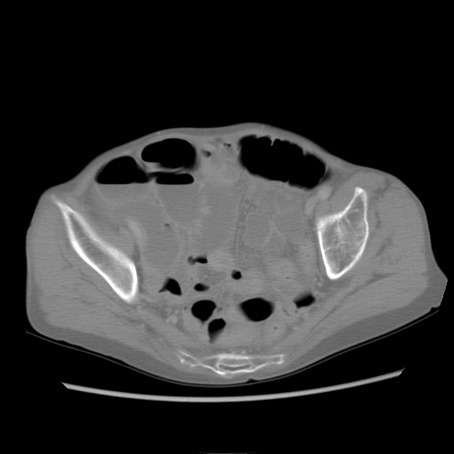

症例25(横断像)

【症例】80歳代女性

【主訴】胸のつかえ感

【現病歴】約9時間前に食後から胸のつかえた感じあり、嘔吐あり、来院。

【既往歴】胃癌(全摘)、胆摘、虫垂炎

【身体所見】心窩部に圧痛あり、反跳痛なし。

【データ】WBC 5700、CRP 0.05